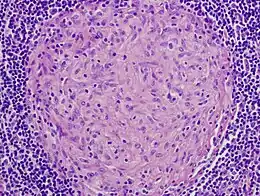

| Picture of a granuloma (without necrosis) as seen through a microscope on a glass slide: The tissue on the slide is stained with two standard dyes (hematoxylin: blue, eosin: pink) to make it visible. The granuloma in this picture was found in a lymph node of a patient with a Mycobacterium avium infection. | |

Granuloma without necrosis in a lymph node of a person with sarcoidosis

Granuloma without necrosis in a lymph node of a person with sarcoidosis Granuloma with central necrosis in a lung of a person with tuberculosis: Note the Langhans-type giant cells (with many nuclei arranged in a horseshoe-like pattern at the edge of the cell) around the periphery of the granuloma. Langhans-type giant cells are seen in many types of granulomas and are not specific for tuberculosis.